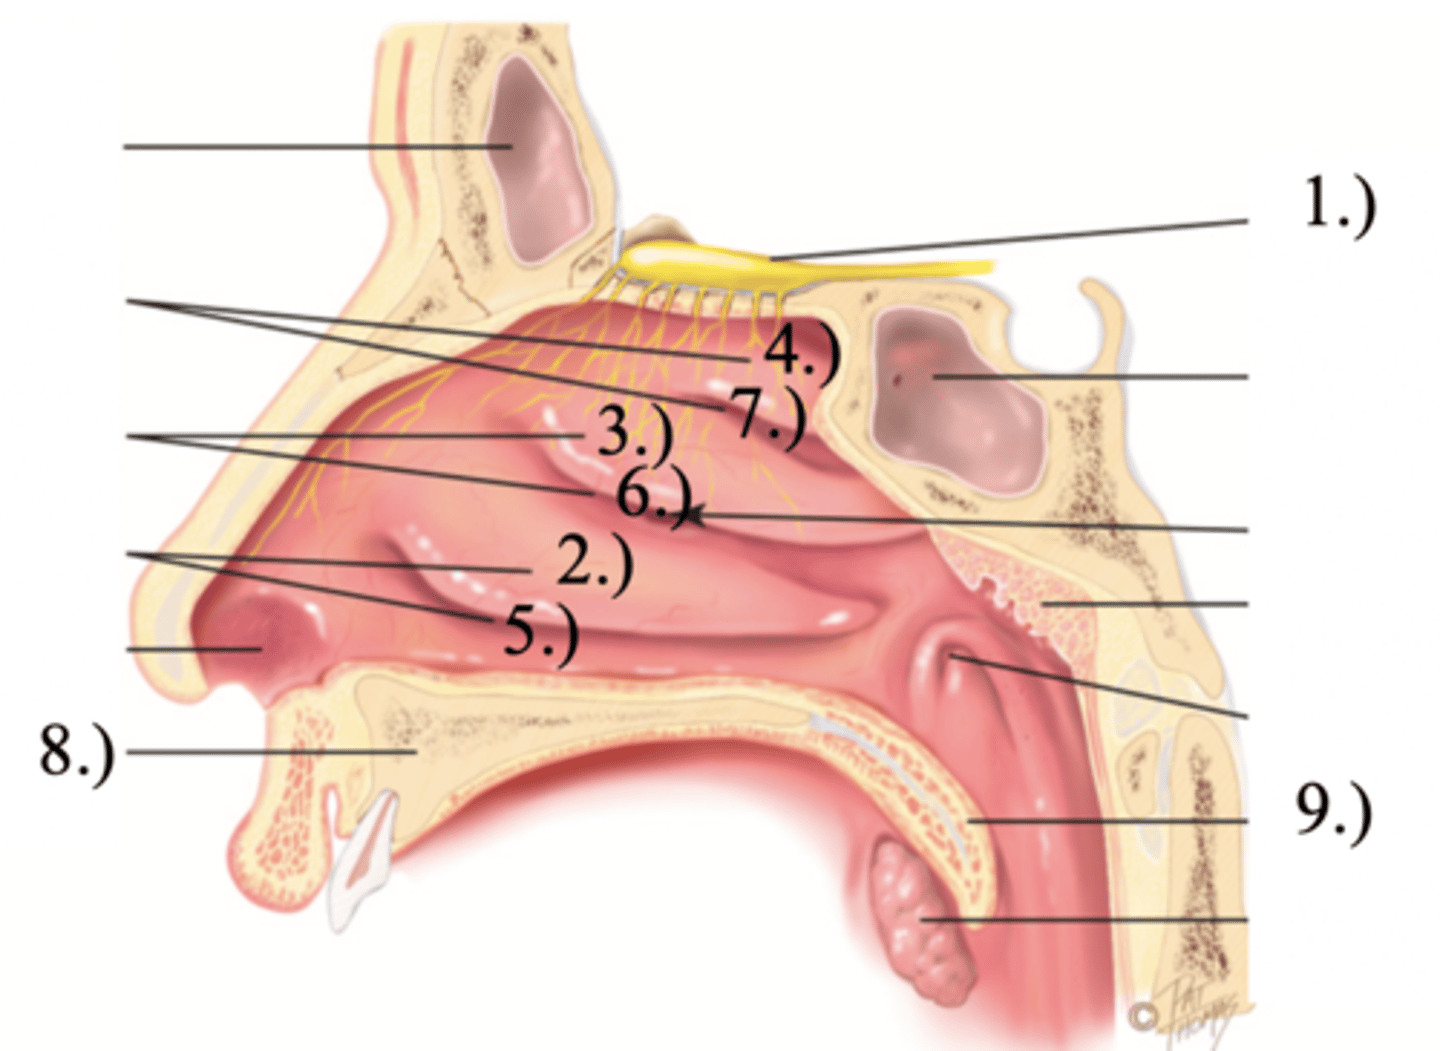

Turbinates (Conchae)

- There's an inferior, middle, and superior one (2.), 3.), 4.))

Olfactory Region

A dime-sized area at the top of each nasal cavity that houses sensors responsible for smell (1.))

Meatuses

- There's an inferior, middle, and superior one

(5.), 6.), 7.))

Anterior palate portion that is supported by the palatine processes of the maxillae and the palatine bones (8.))

Posterior palate portion, not supported by bone (9.))